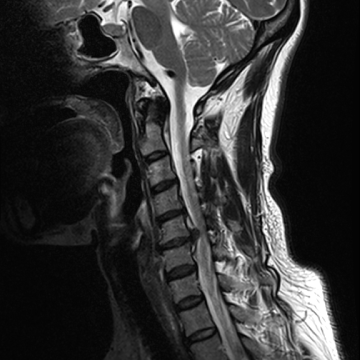

목디스크

척추뼈 사이사이에 무게와 충격을 흡수할 수 있는 연골조직을 디스크, 즉 경추 추간판이라 합니다.

목의 무리한 사용이나 잘못된 자세, 퇴행성 변화 등으로 인해 디스크 안에 있는 수핵이 밖으로 탈출하게 되어 신경을 누르는 경추 추간판 탈출증을 목 디스크라 합니다.

질환을 의심해 볼 수 있는 자가진단법으로 정확한 진단은 MRI와 같은 영상학적 검사를 필요로 합니다.

목디스크 치료법

목디스크가 심각하지 않은 경우에는, 신경 유착을 제거해 주는

신경성형술, 고주파를 쏘아 튀어나온 디스크와 염증을 가라앉히는

고주파 수핵성형술과 같은 비수술 치료를 통해 완화가 가능합니다.

비수술적 치료 효과가 없거나 디스크의 신경 압박이 심한 경우는

미세현미경수술, 인공디스크 치환술, 경추유합술을 통해 치료가 가능합니다.